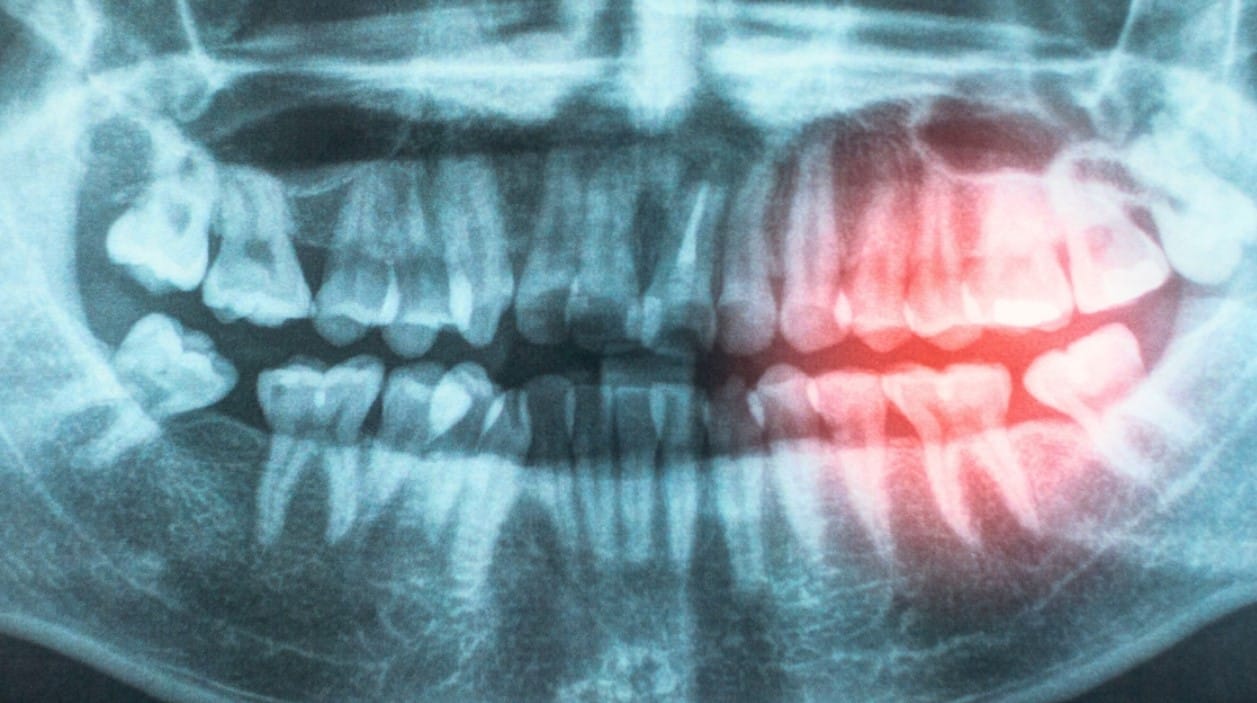

Bakteriler, Kan Dolaşımı ve Kronik İnflamasyon

Raporda öne çıkan temel mekanizmalardan biri, ağız içindeki bakterilerin hasar görmüş ve kanayan diş etleri yoluyla kan dolaşımına girmesi. Bu durum, vücutta kronik inflamasyonu (uzun süreli iltihabi yanıt) tetikleyebiliyor. Kronik inflamasyonun ise damar duvarlarına zarar vererek ateroskleroz gelişimine katkı sağladığı uzun süredir biliniyor.

“Ağzınız ve kalbiniz birbiriyle bağlantılıdır. Diş eti hastalığı ve kötü ağız hijyeni, bakterilerin kan dolaşımına girmesine izin vererek inflamasyona neden olabilir; bu da damarları zedeleyip kalp hastalığı riskini artırabilir.”